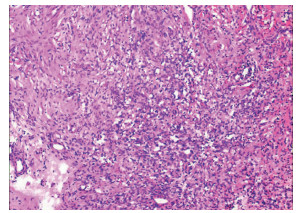

Lymphoepithelioma-like hepatocellular carcinoma: A case report

Xiaotong QIU, Zhengqi WU, Xuxiang XIA, Guoyue LYU

2022, 38(3): 634-635. DOI: 10.3969/j.issn.1001-5256.2022.03.027

Abstract(762) HTML (934) PDF (2924KB)(68)

Abstract: